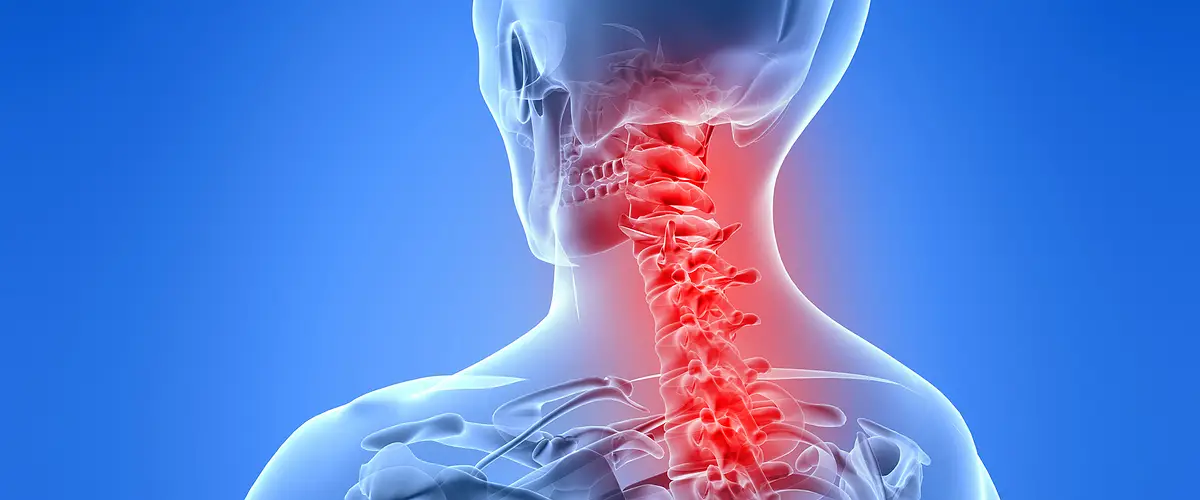

목디스크는 목의 디스크가 손상되어 발생하는 질환으로, 주로 심한 목 통증과 불편함을 유발합니다. 특히 현대 사회에서는 전자 기기를 많이 사용하는 사람들에게 더욱 유용한 정보가 될 수 있습니다.

목디스크 증상

- 1. 목 통증

목디스크로 인해 한쪽 또는 양쪽 목에 다양한 정도의 통증이 발생할 수 있으며, 이는 일상생활에 큰 불편을 초래할 수 있습니다. 통증은 지속적일 수도 있고, 특정 동작에서 심화될 수도 있습니다.